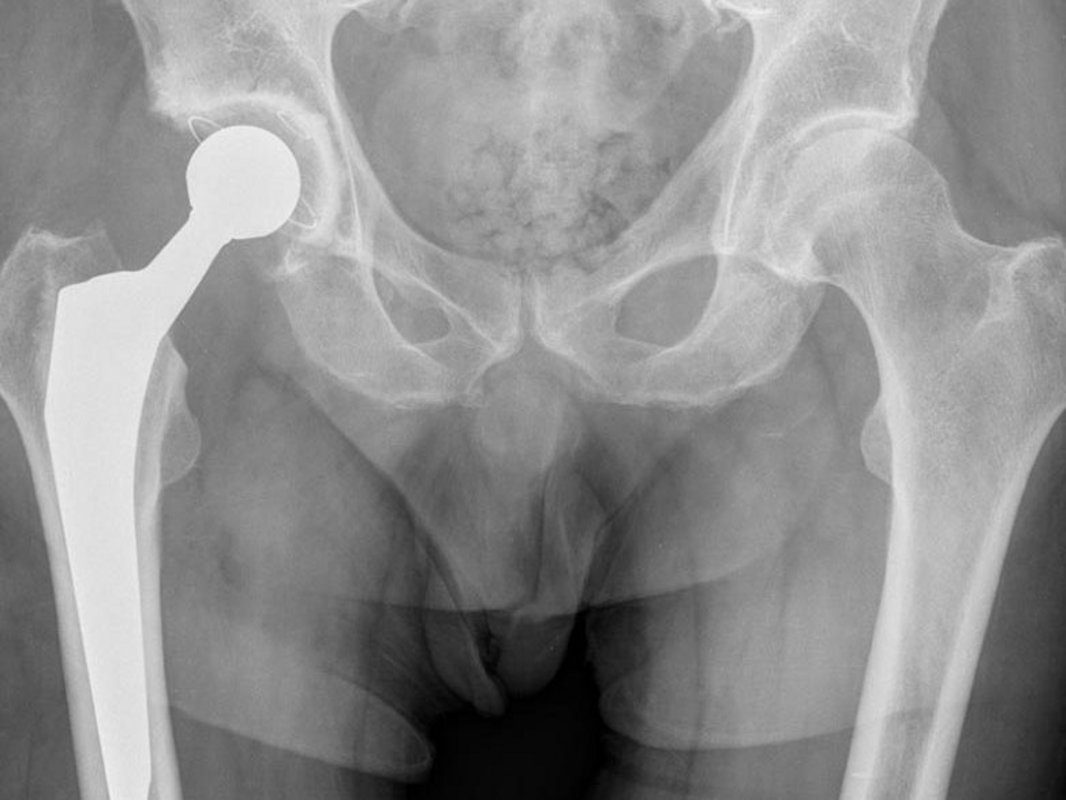

Im Röntgenbild erkennt man dann eine zunehmende Verschmälerung des Gelenkspalts, eine Verdichtung des gelenknahen Knochens, eine Deformierung und knöcherne Anbauten.

Bei Verschleiß der Hüfte, entsprechendem Leidensdruck und nicht mehr ausreichend ansprechender konservativer Therapie kann die Implantation einer Hüftendoprothese zu einer deutlichen Verbesserung der Lebensqualität führen.

Zum Einsatz kommen moderne zementfreie und zementierte Endoprothesen, die in einer Vielzahl von Registern besonders gute Ergebnisse gezeigt haben. Insbesondere bei jüngeren und aktiven Menschen werden auch Spezialendoprothesen wie die Hüftkappenendoprothesen oder Oberflächenersatzprothesen nach McMinn oder Schenkelhalsprothesen implantiert, um für den Fall einer hoffentlich nie auftretenden Revision genügend Knochenstock zu erhalten. In schwierigen Fällen erfolgt die Implantation mit Navigation. Bei speziellen anatomischen Situationen wird unter Umständen eine individuell für den Patienten angefertigte Endoprothese verwendet.

Hüftendoprothesen werden während eines 8- bis 12-tägigen stationären Aufenthaltes implantiert. Die Operation selbst dauert meistens etwa eine Stunde. Der Eingriff erfolgt in Vollnarkose oder in Rückenmarksanästhesie (Spinalanästhesie). Verschiedene Zugänge sind möglich. Je nach Vor- und Nachteilen werden bei uns anteriore (vordere), anterolaterale (vorne seitliche), seitliche und hintere Zugänge verwendet. Stets achten wir darauf, den Zugang möglichst klein zu halten und insbesondere die Muskulatur zu schonen. Zunächst werden erkrankte Knochen und Knorpel des Gelenkes entfernt, dann wird zunächst eine Hüftgelenkspfanne mit Inlay eingesetzt und schließlich ein Prothesenschaft verklemmt oder einzementiert. Ein aufgesetzter Kugelkopf erlaubt schließlich wieder ein harmonisches Bewegen. Im Regelfall ist der Blutverlust bei diesen Operationen gering, sodass keine Blutkonserven erforderlich werden. Zum Wohl unserer Patienten sammeln wir das Blut schon während der Operation und in den ersten sechs Stunden danach. So können wir es im Bedarfsfall aufarbeiten und retransfundieren. Dies bedeutet, dass wir nur sehr selten Fremdblut einsetzen müssen.